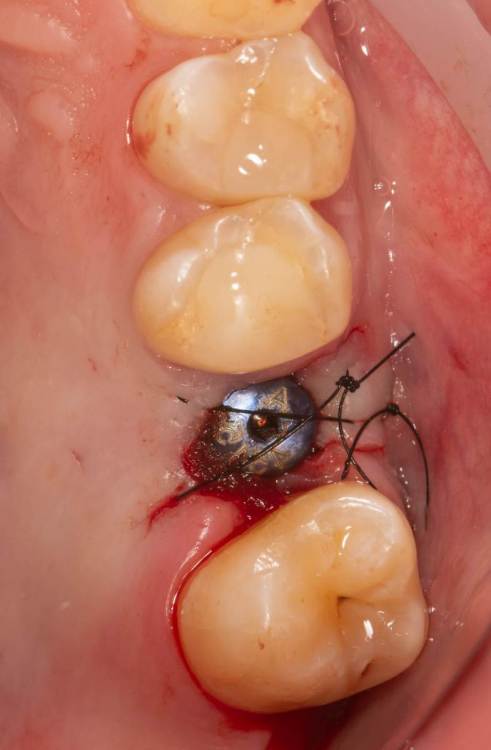

Женька Опубликовано 23 августа, 2022 Поделиться Опубликовано 23 августа, 2022 Собственно в первый же день после отпуска взял потестить к себе, тк тушку пока ещё не приобрели. По кейсу: ставили снукон в апреле с ЗСЛ, Поставив, понял что позиция для протезирования мне не понравилась, решил немного изменить угол, попытался выкрутить и в следующее мгновение уже вижу имплантат "валяется" в субантральном пространстве (ЗСЛ без графта делал). Перешли на ОСЛ, уложил Лиопласт, заглушка. Спустя 4 месяца открытие. Остальное на фотках. К сожалению первую операцию не протоколировал :(. Что скажете? Вроде резкий?) 3 Ссылка на комментарий